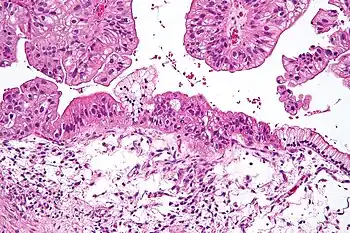

| Micrograph of a mucinous ovarian carcinoma stained by H&E | |

Epithelial carcinoma

Epithelial ovarian cancer typically presents at an advanced stage and is derived from the malignant transformation of the epithelium of the ovarian surface, peritoneum, or fallopian tube.[67] It is the most common cause of gynecologic cancer death.[67] There are various types of epithelial ovarian cancer, including serous tumor, endometrioid tumor, clear-cell tumor, mucinous tumor, and undifferentiated or unclassified tumors.[68] Annually worldwide, 230,000 women will be diagnosed and 150,000 will die.[69] It has a 46% 5 year survival rate after diagnosis because of the advanced stage of the disease at the time of diagnosis.[69] Typically, around 75% of patients are diagnosed as having an advanced stage of the disease because of the asymptomatic nature of its presentation.[69] There is a genomic predisposition to epithelial ovarian cancer and the BRCA1 and BRCA2 genes have been found to be the causative genes in 65-75% of hereditary epithelial ovarian cancer.[69]

Mucinous

Mucinous tumors include mucinous adenocarcinoma and mucinous cystadenocarcinoma.[29]

Mucinous adenocarcinoma

Mucinous adenocarcinomas make up 5–10% of epithelial ovarian cancers. Histologically, they are similar to intestinal or cervical adenocarcinomas and are often actually metastases of appendiceal or colon cancers. Advanced mucinous adenocarcinomas have a poor prognosis, generally worse than serous tumors, and are often resistant to platinum chemotherapy, though they are rare.[29]